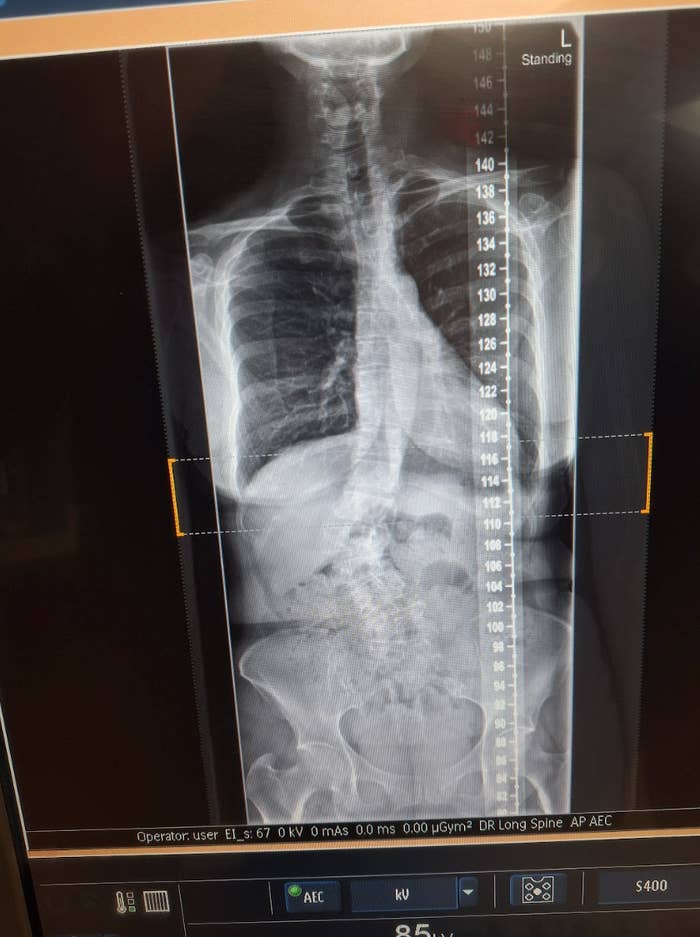

“That’s not me,” I protested, straightening my strained spine. I didn’t have anatomical terms for what I refused to see — the lower backbone bowed to the right in the shape of a capital C; the middle spine jogged to the left off-plumb; the shoulders and hips were cockeyed. “You got the X-rays mixed up.”

“Sorry, it is,” the doctor traced the curve with his finger. “Bordering on severe scoliosis.”

An X-ray of the author's spine taken in 2023.

“See, here?” The spine surgeon pointed to the new set of X-rays. “Serious lumbar curve of 45 degrees, apex here at L4, then a 20-degree rotation at T2 and T3. That’s where you get your disk compression and nerve impingement causing neuropathy in the legs.”

“Neuropathy,” I murmured in a cortisol-infused daze. It was like seeing the snaking horror inside me for the very first time.